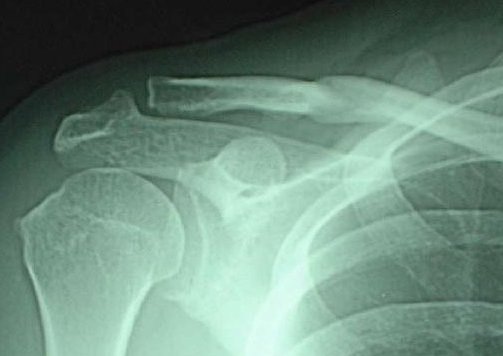

実は5月1日に、自転車に乗っていて、突然茂みから出現した小学校5年生の男子の突進を自転車のよこっぱらに受け、宙を舞ってアスファルト地面に右肩から落ちて、右の鎖骨を骨折してしまったのだった。左手で触ってみると、なにか突き出ているので、これは骨折したなと思い、自分で救急車を呼んで(初めて乗ったぜ)病院に運んでもらった。

脱臼だったら、手術をしなければいけなかったと医者に言われた。むしろ骨折の方がよかったというような口ぶりで、今はギブス固定ではなく、鎖骨バンドで両肩を固定する治療法が主流みたいで、私もそういう鎖骨バンドを装着させられた。

骨はひっついてもいびつにひっついていて(入という字のような引っ付き方)、その箇所がぼこっと飛び出しているのが、はっきりと分かるのだが、医者は「あなたは若い女性じゃないし、鎖骨をみせるような衣装を着ることもないし、それでいいのだ」と言われたので、そんなもんなのか、と思い、ずっと生活してきたが、慢性化した痛みに耐えなくてはならないのは、「なんに対する応報」なのかと思ったりもする(まああれこれ思うことはあるが)。

以下はネットから拾ってきた写真、折れ方がよく似ているので掲げておくよ。